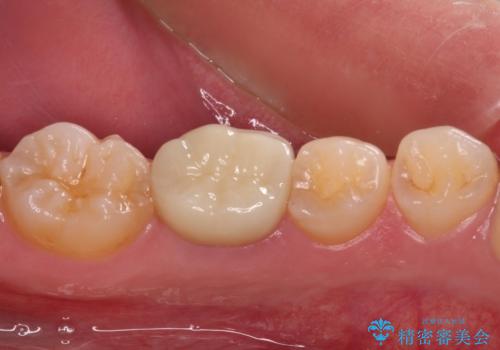

患者様と相談し、根管治療を再度行った後、フルジルコニアクラウンにて補綴治療することとしました。

フルジルコニアクラウンを装着したことにより、舌感が改善されるとともに、むし歯再発リスクを軽減することができました。